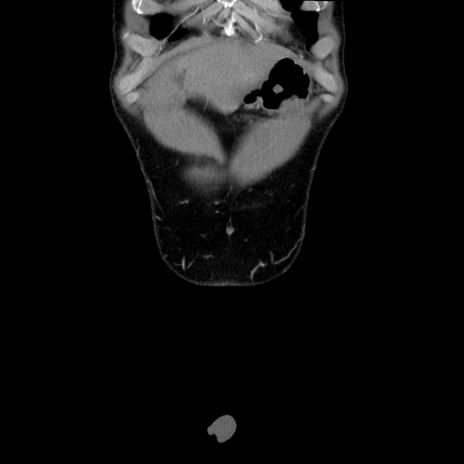

症例36(冠状断像)

【症例】20歳代 男性

【主訴】心窩部痛

【現病歴】今朝より上腹部痛あり。一旦軽快していたが再度出現したため救急要請。昨日夕に白身の魚を含む刺身を食べた。

【身体所見】BP 136/89mmHg、HR 74/min、BT 37.0℃、腹部:膨満、軟、心窩部に圧痛あり。反跳痛なし、筋性防御なし、腸雑音やや亢進あり。

【データ】WBC 17700、CRP 0.48